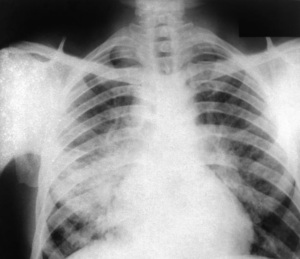

Sie sind hier: Startseite Nachrichten Gesundheit Raman-Spektroskopie: Ersatz für Röntgenstrahlen Röntgenbild: Alternative Untersuchungsmethode in Sicht. Bild: CDC/ Dr. P. Brachman

Röntgenbild: Alternative Untersuchungsmethode in Sicht. Bild: CDC/ Dr. P. Brachman